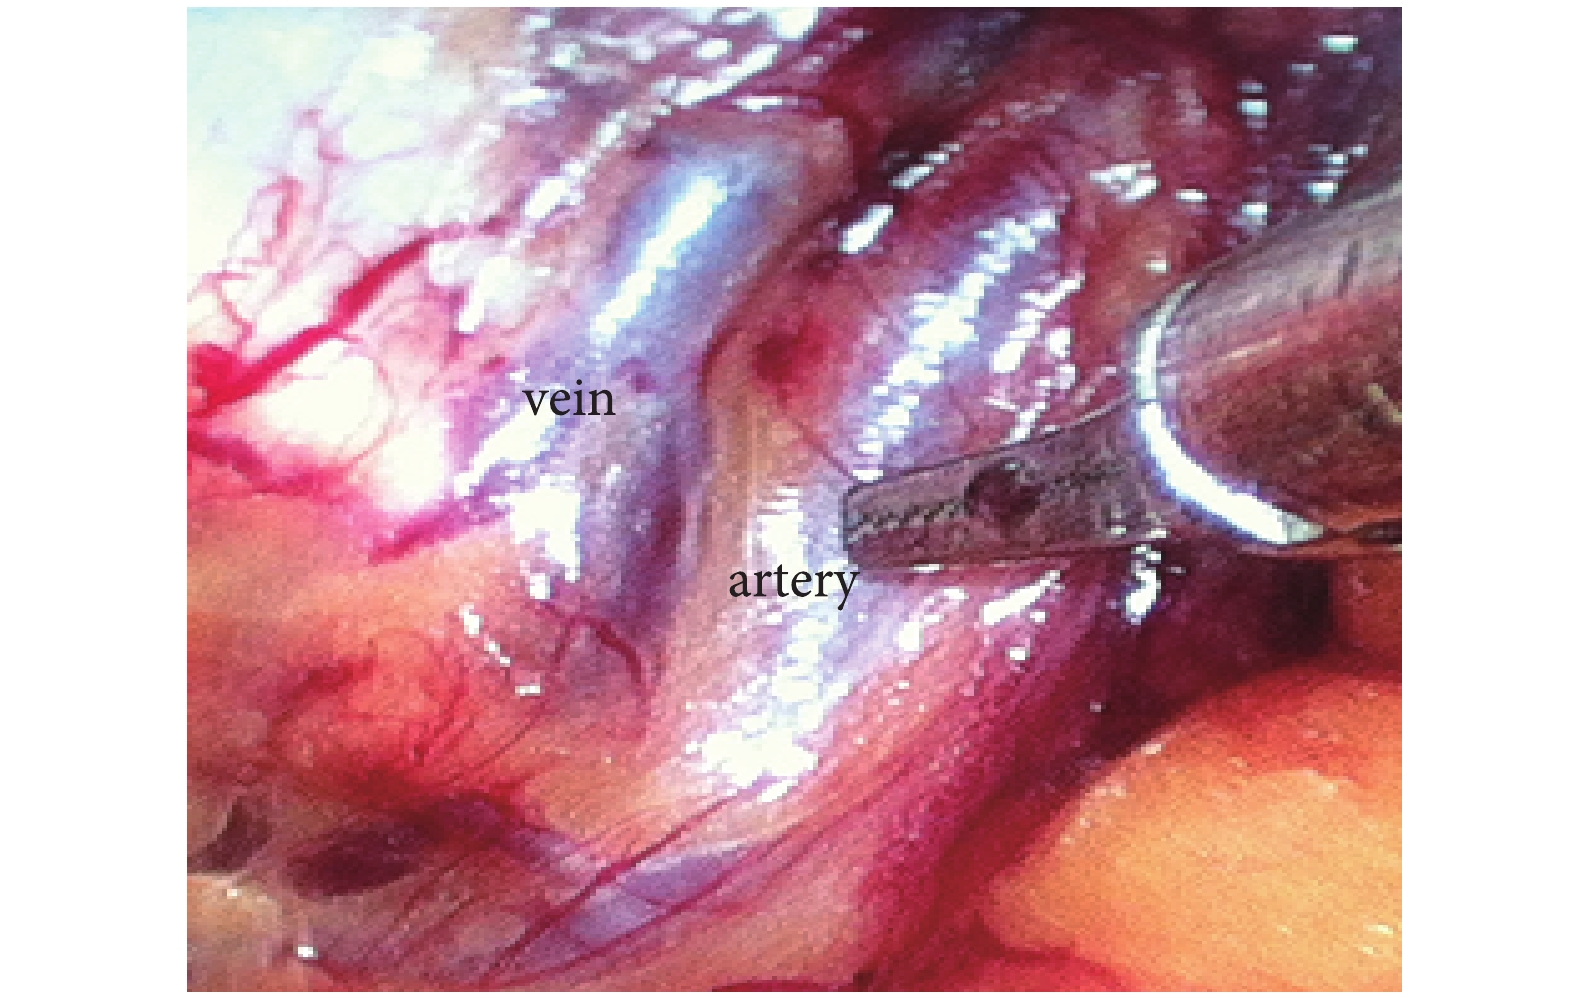

恥骨吻合支表面至少 1 條死冠血管(動脈或靜脈)出現率為 61.5%(32/52),死冠動脈出現率為 46.2%(24/52),死冠靜脈出現率為 34.6%(18/52),死冠動靜脈同時出現率為 25.0%(13/52),死冠動脈出現率明顯高于靜脈出現率(P<0.05)。死冠血管距離為(54±4.8)mm,死冠動脈距離和靜脈距離比較差異無統計學意義〔(53±5.2)mm 比(54±5.7)mm,t=0.076,P>0.05〕。死冠動脈直徑明顯小于靜脈直徑〔(3.2±0.3)mm 比(3.4±0.4)mm,t=2.231,P<0.05〕。典型病例見圖 1、2。